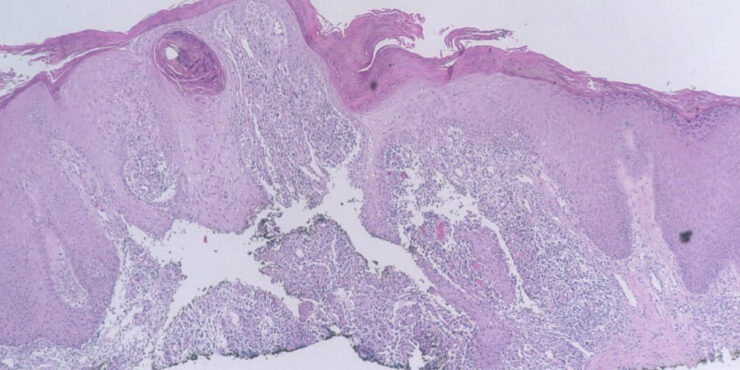

Read MoreMunro microabscesses in Psoriasis = خراجات مونرو المجهرية في الصدف Psoriasis Psoriasis may be divided into psoriasis vulgaris, generalized pustular psoriasis, and localized pustular psoriasis. Psoriasis Vulgaris Clinical Features Psoriasis vulgaris is a common chronic inflammatory skin disorder that affects approximately 1.5% to 2% of the population in the Western countries. It is characterized by […]